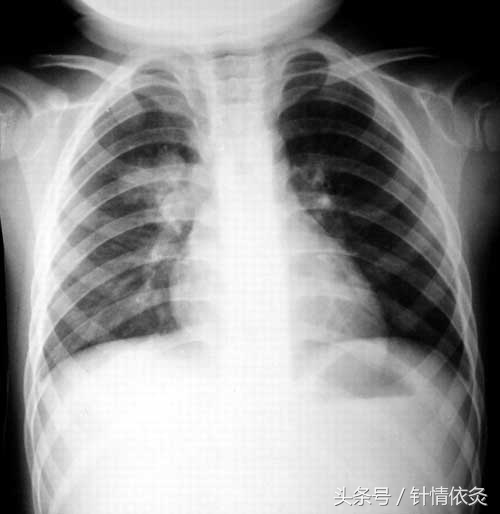

小儿肺炎又称小儿急性肺炎、小儿急性支气管肺炎,是一年四季均可发生,尤以冬春季发作为多的临床常见病。临床症状主要表现为发热、咳嗽、咳痰、气促、呼吸困难、肺部可闻及中细湿罗音,精神萎靡,食欲不振,烦躁不安,轻度腹泻或呕吐等。胸部X线、病毒病原学、白细胞等检查和C反应蛋白试验可以辅助确诊。需与支气管炎、急性粟粒型肺结核、干酪性肺炎、支气管异物、毛细支气管炎、小儿感冒等病症相鉴别。